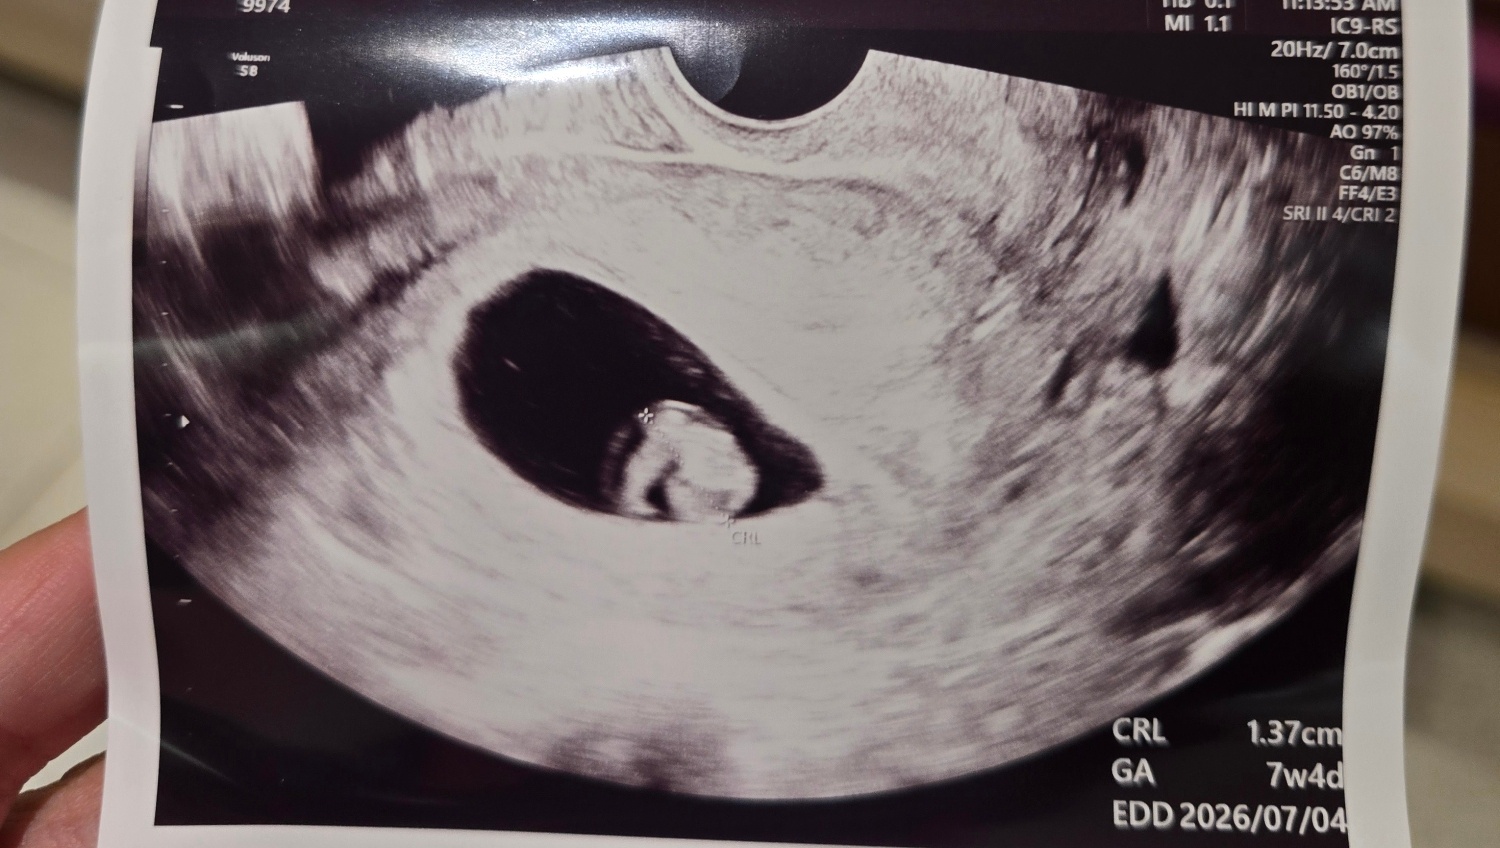

7주4일차!

우리 애기 머리보고왔어요!! 전 지금까지 입덧이나 이런증상들이없어서 괜찮은걸까하고 걱정많이했는데 ㅎㅎㅎ제걱정과는 다르게 잘커주고있네요 다음주엔 젤리곰이되어있겠죠?